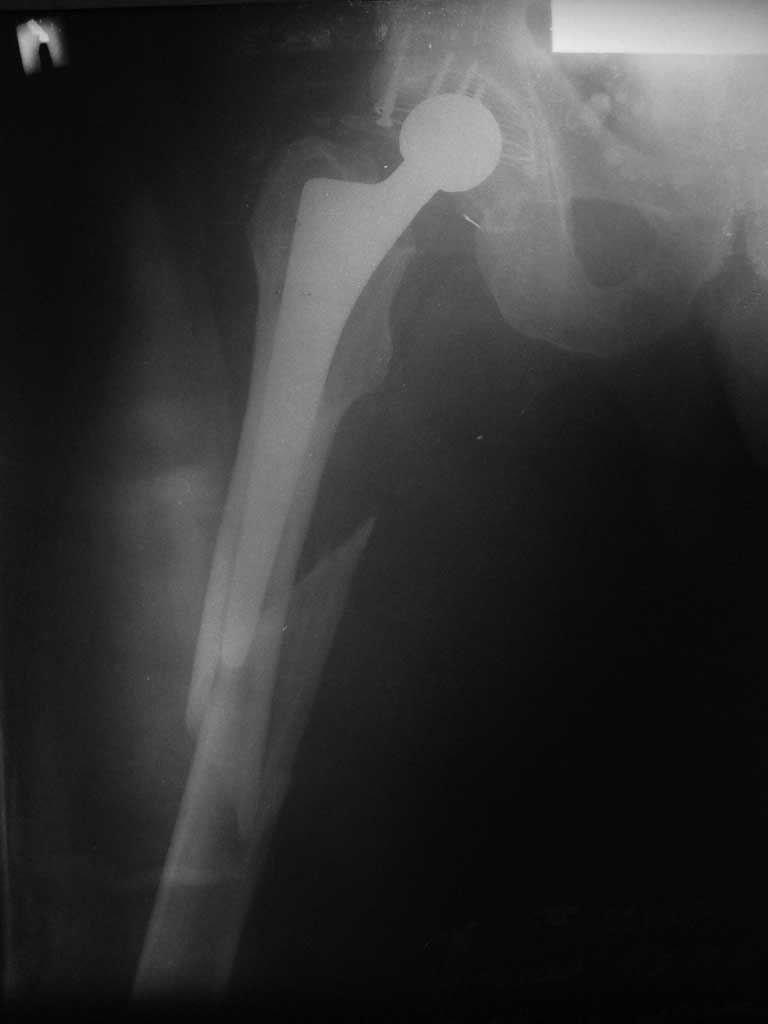

Пациенту 72 года, оперировался 11 лет назад в ГКБ15 Москва. Судя по снимку ножка споторно фирмы матис. Вряд ли сможем найти такую же для примерки.

Дополнительные снимки